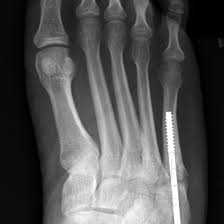

The sutures in the small incision will need to be removed after 10 to 14 days. See more ideas about fracture healing, jones fracture, fracture. These are notorious for very slow healing. What is the recovery time of a broken ankle? Do you have a jones fracture of the 5th metatarsal? Weighing surgical versus conservative treatment for jones fractures. Well find out exactly how to get this bone feeling better! This is an ap view of a percutaneous jones fracture surgery. Outside of the foot pain can be improved with a few simple treatment. While people can relate to a stubbed toe or sprained ankle; Surgical treatment of femoral neck fracture. 5th metatarsal fracture recovery time: A jones fracture occurs in a region known as the the incision required to repair a jones fracture is small and the surgery can be done as an outpatient procedure under general or local anesthesia.

Intramedullary Screw Fixation Of Proximal Fifth Metatarsal Fractures In Athletes from www.scielo.br Lengthy healing times and risk of refracture may be reasons for surgical repair in these fractures. A foot can be broken in many places learn about the jones fracture, what types of treatments are available, and if jones fracture surgery is the best treatment option. Patient may be in a removable boot after surgery for a week or two at the direction of the physician. Jones fractures are named after sir robert jonestrusted source , an orthopedic surgeon who in 1902 reported on his own injury and the injuries of several people he. Do you have a jones fracture of the 5th metatarsal? Jones fracture surgery recovery on mainkeys. A jones fracture is a break between the base and middle part of the fifth metatarsal of the foot. Yet surgery is not always necessary.